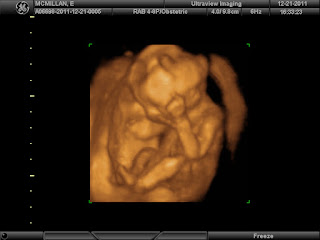

How far along? 18 weeks! Almost half way! wowzers!!!

Baby size: 5.6 inches or the size of a sweet potato or bell pepper!

Baby weight: 6.7oz

Gender: GIRL!